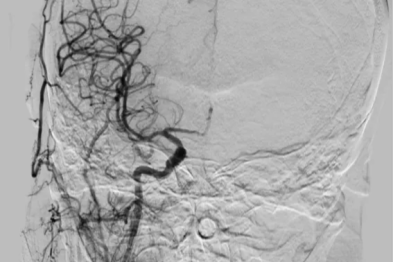

德达 MDT 精准狙击罕见血管病变,点亮绝境求医路

心脏「泵血」仅 20%!七旬老人突发脑栓塞,多学科联手闯过生死关